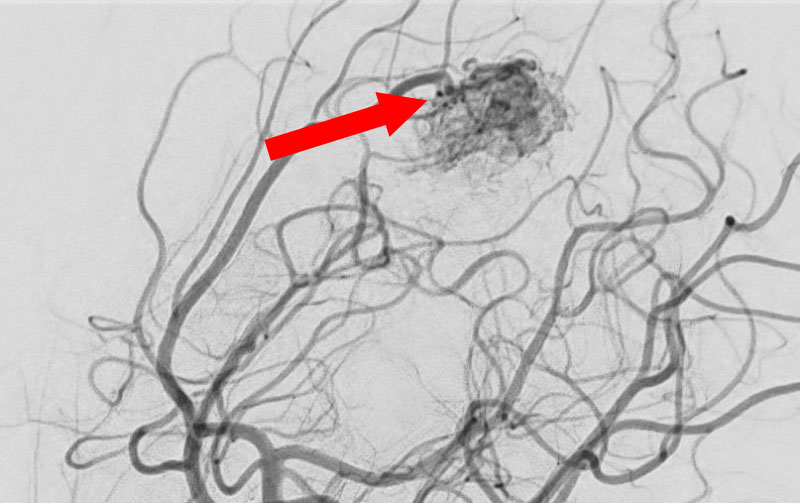

'25年10月

脳動静脈奇形

50代

大阪府の病院

No.1585 手術前

No.1585 手術中

No.1585 手術後